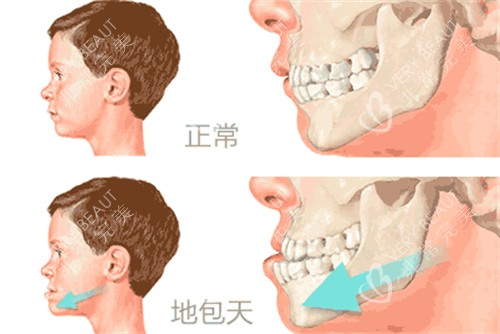

牵张成骨术特别适用于儿童,因为儿童的骨骼生长活跃,组织再生能力强,术后改善比较快,结果更显著。然而,在某些特定情况下,成年人也可以接受牵张成骨术,尤其是那些骨骼未完全闭合或具有强烈改善需求的个体。

颅面畸形矫正:如小下颌畸形(mandibular micrognathia)、半侧颜面发育不全综合症(hemifacial microsomia)以及各种颅面畸形综合症,如Nager syndrome、Pierre-Robin syndrome、Crouzon syndrome、Treacher-Collins syndrome、Craniofacial synostosis等。

其他适应症:如颞下颌关节强直后畸形、创伤后生长障碍等,牵张成骨术同样可以发挥重要作用。